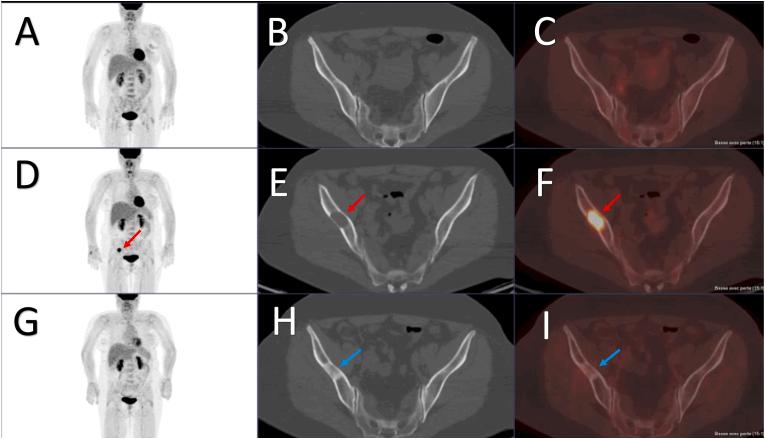

Regarding initial staging of patients with NST BC, [F]FDG PET/CT is the preferred modality in the EANM-SNMMI guideline, showing superiority as a single modality to a combination of contrast-enhanced CT of thorax-abdomen-pelvis plus bone scan in head-to-head comparisons and a randomized study. Its use is recommended in patients with clinical stage IIB or higher and may be useful in certain stage IIA cases of NST BC. In NCCN, ESMO, and ABC guidelines, [F]FDG PET/CT is instead recommended as complementary to conventional imaging to solve inconclusive findings, although ESMO and ABC also suggest [F]FDG PET/CT can replace conventional imaging for staging patients with high-risk and metastatic NST BC. During follow up, NCCN and ESMO only recommend diagnostic imaging if there is suspicion of recurrence. Similarly, EANM-SNMMI states that [F]FDG PET/CT is useful to detect the site and extent of recurrence only when there is clinical or laboratory suspicion of recurrence, or when conventional imaging methods are equivocal. The EANM-SNMMI guideline is the first to emphasize a role of [F]FDG PET/CT for assessing early metabolic response to primary systemic therapy, particularly for HER2+ BC and TNBC. In the metastatic setting, EANM-SNMMI state that [F]FDG PET/CT may help evaluate bone metastases and determine early response to treatment, in agreement with guidelines from ESMO.

对于 NST BC 患者的初始分期,[F]FDG PET/CT 是 EANM-SNMMI 指南中的首选方法,在头对头比较和随机研究中,作为单一方法,其显示出优于对比增强 CT 联合胸部-腹部-骨盆加骨扫描的优越性。建议在临床分期 IIB 或更高的患者中使用,并且在某些 NST BC 的 IIA 病例中可能有用。在 NCCN、ESMO 和 ABC 指南中,[F]FDG PET/CT 被建议作为常规成像的补充,以解决不确定的发现,尽管 ESMO 和 ABC 也建议[F]FDG PET/CT 可用于分期高危和转移性 NST BC 患者。在随访期间,NCCN 和 ESMO 仅建议在怀疑复发时进行诊断性影像学检查。同样,EANM-SNMMI 指出,只有在临床或实验室怀疑复发时,或当常规影像学方法不确定时,[F]FDG PET/CT 才有助于检测复发的部位和范围。EANM-SNMMI 指南是第一个强调[F]FDG PET/CT 在评估原发性全身治疗早期代谢反应中的作用的指南,特别是对于 HER2+BC 和三阴性 BC。在转移性环境中,EANM-SNMMI 指出,[F]FDG PET/CT 可帮助评估骨转移并确定对治疗的早期反应,与 ESMO 的指南一致。